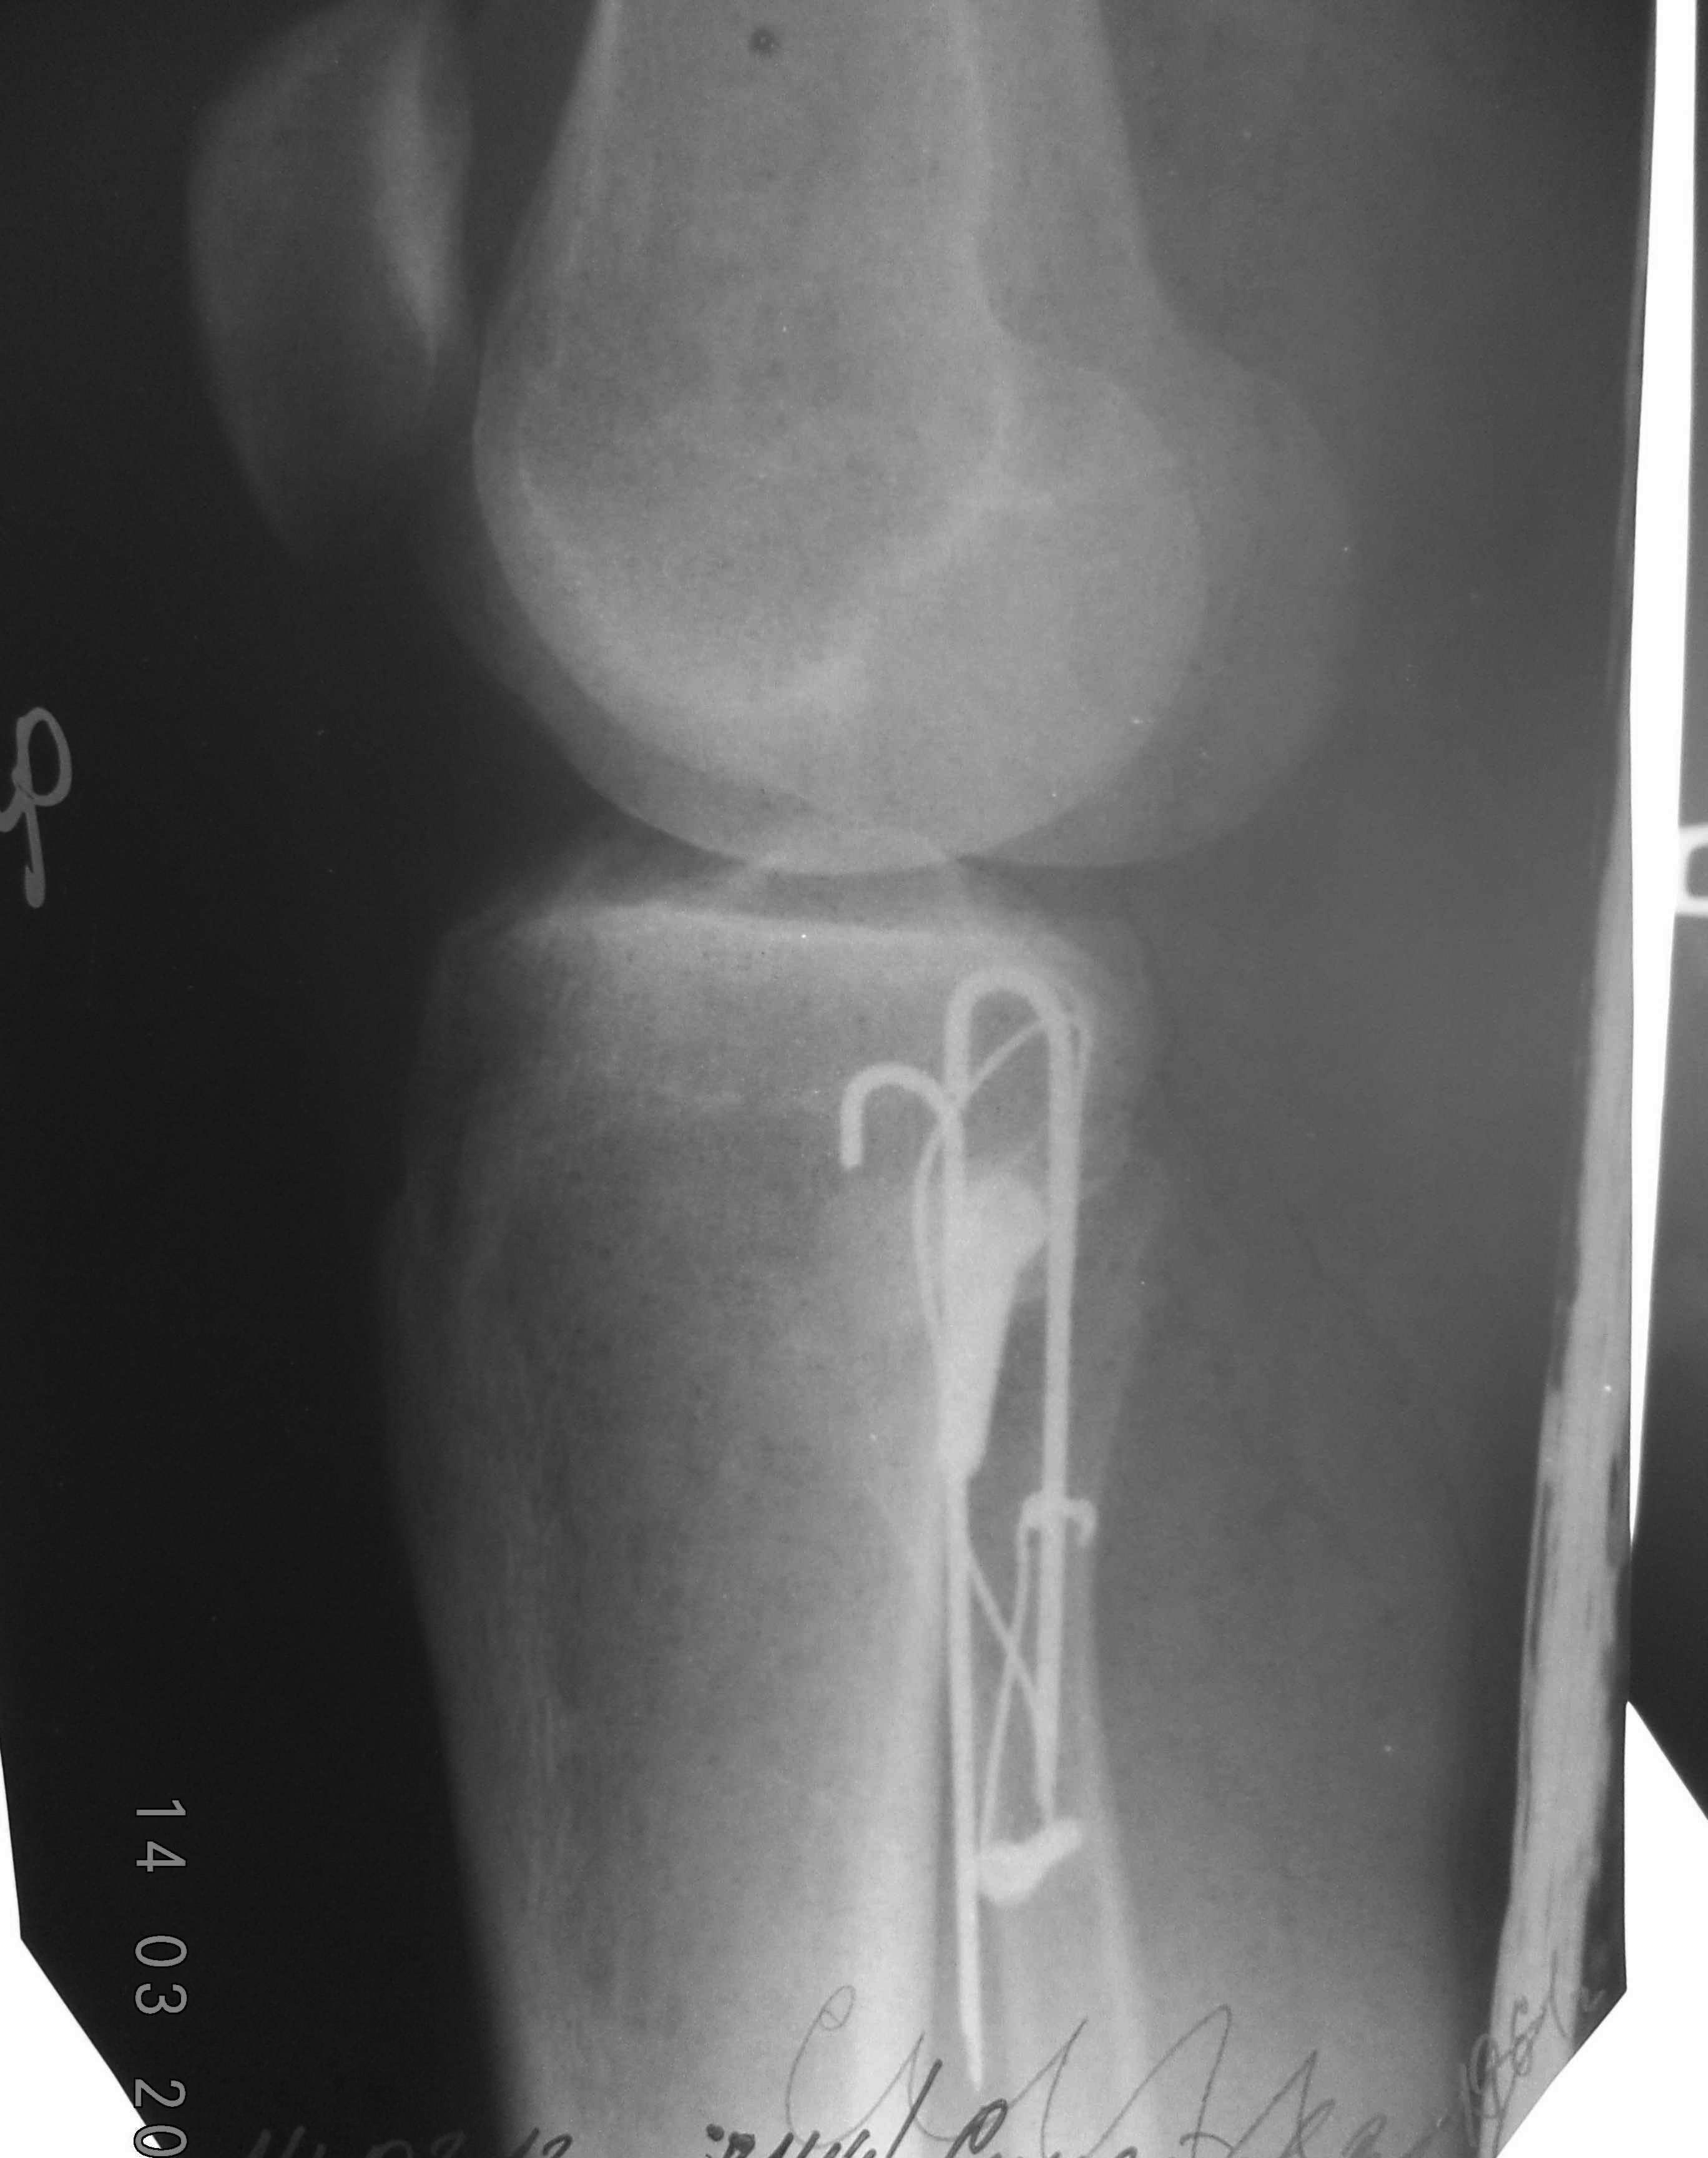

Вторая проекция.

Неврит должен пройти. По картинке симпатично.

К сожаленью, неврит не пройдет. Проволочная петля аккурат лежит по наружной поверхности малоберцовой кости, придавив мышечные ветви малобецового нерва.

С уважением, Бехтерев Антон.